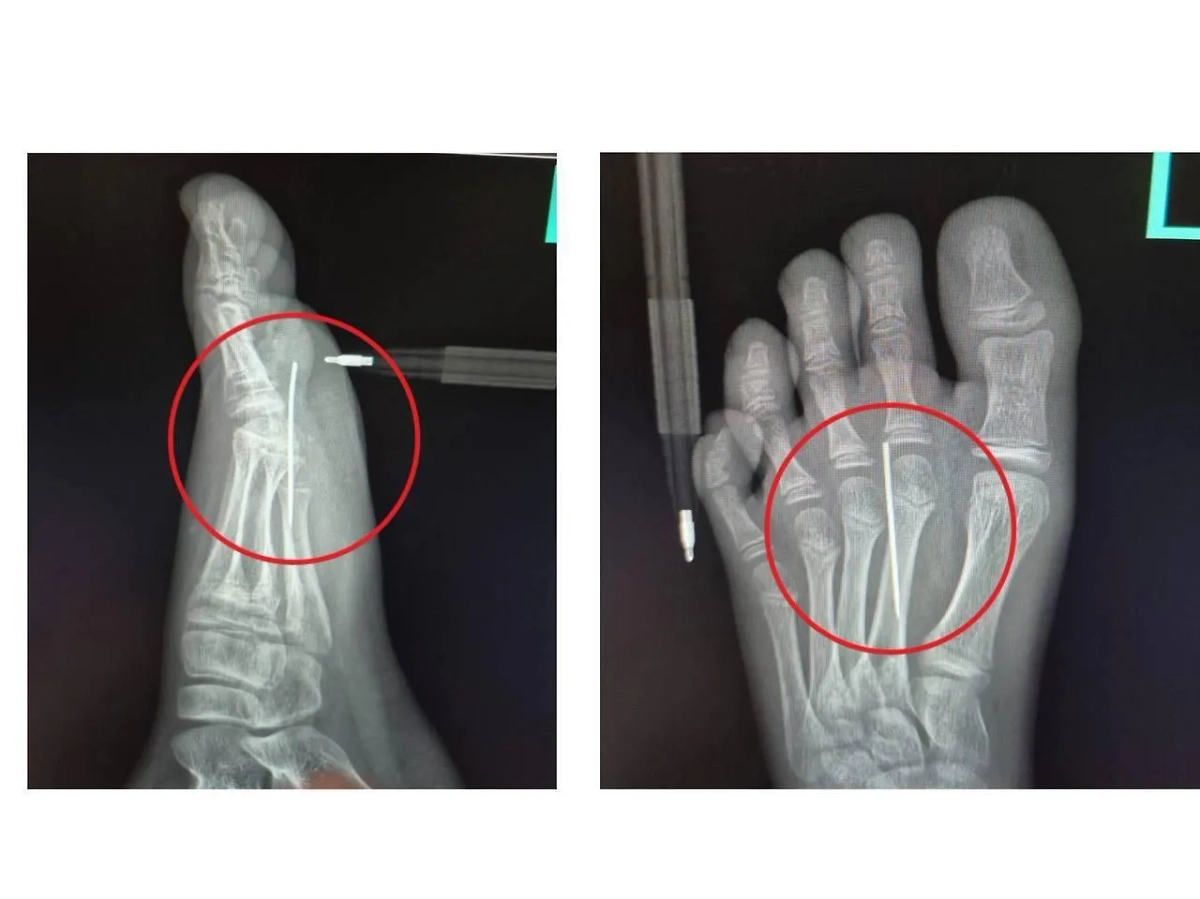

Заведующий травматологическим пунктом Артём Лисенков рассказал, что в больнице врачи сделали рентген, который подтвердил наличие инородного тела в стопе. Иглу аккуратно достали специальным инструментом «Москит». Процедура заняла не больше 3 минут и прошла успешно. Спустя несколько часов пациента уже выписали домой.